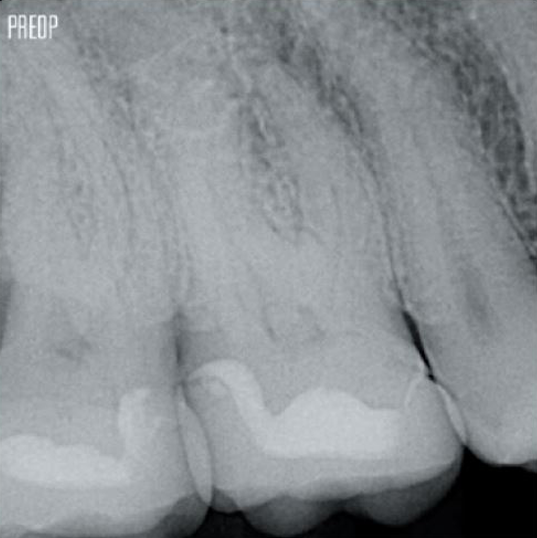

Fotos cortesía del Dr. Ahmed Salman

Más conservación de dentina. Se garantiza la conformación, irrigación y obturación adecuadas.